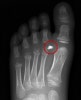

1. Glass foreign body

DP view : It is not possible to establish the location of a foreign body without reference to at least 2 images.

On this image alone it is not possible to determine if this glass foreign body is located on the dorsal or plantar side of the foot.